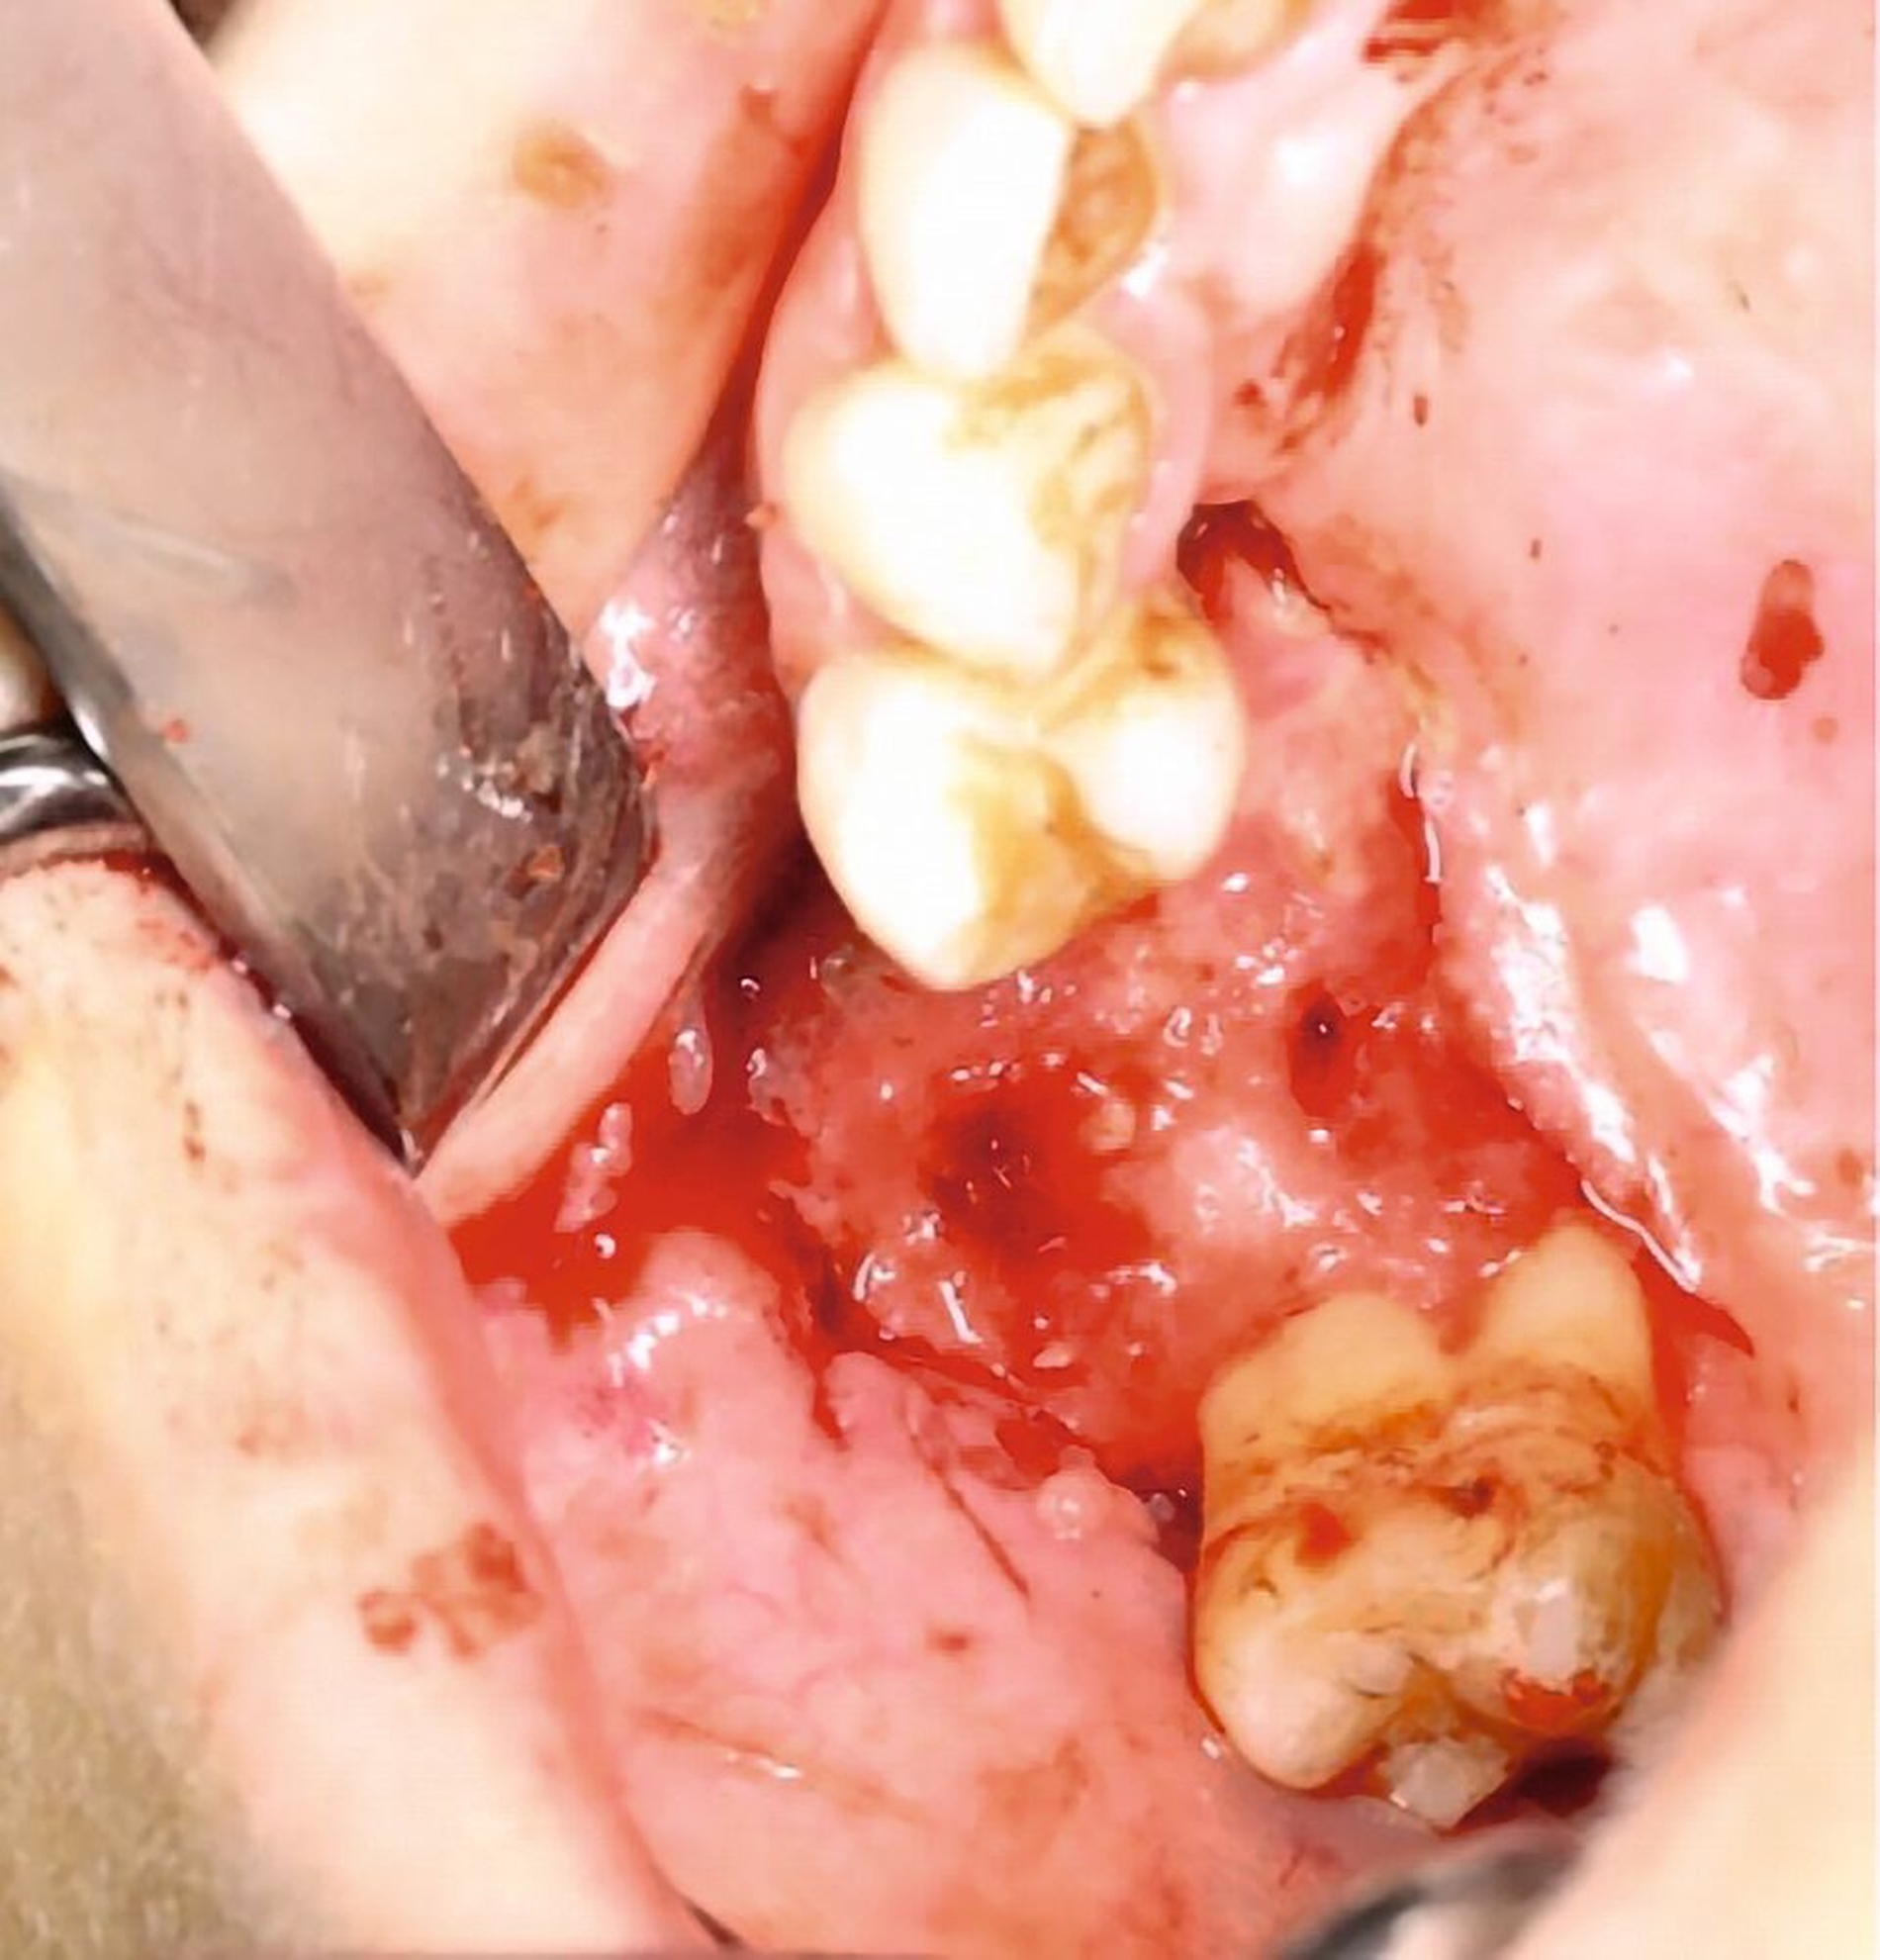

Das DVT zeigte eine Spiegelbildung im rechten Sinus maxillaris, jedoch keinen stark auffälligen knöchernen Befund (Abbildung 2). Die Patientin wurde zu intravenöser Antibiose, Analgesie und Ernährung über eine nasogastrale Sonde stationär aufgenommen. Im Verlauf wurde eine Verbandsplatte per Intraoralscan angefertigt und eine Operation zur Nekrosektomie und Wundanfrischung geplant. Zum Zeitpunkt des operativen Eingriffs hatten sich bereits Teile der vestibulären und der palatinalen Schleimhaut abgelöst. Nach Debridement zeigte sich ein großflächiges Areal mit freiliegendem Knochen. Der Zahn 15 wurde bei Lockerungsgrad III entfernt (Abbildung 3).